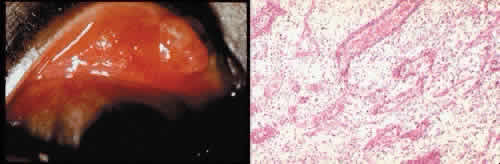

GLAUCOMA SURGICAL PROCEDURES

Cyclocryotherapy, cyclodiathermy (Fig. 20), and therapeutic ultrasonography apply energy directly to the pars plicata and cause lysis of the ciliary muscle and occlusion of the vascular supply, leading to extensive necrosis and scarring. Pressure lowering is accomplished by a reduction of aqueous production. Heat applied to the sclera may cause necrosis and localized scleral thinning. Cold applied to the sclera, unless extreme, does not cause any clinical or histologic changes.

Fig. 20. Cyclodiathermy treatment of the ciliary body to control glaucoma. A. Gross photograph illustrates extensive areas of depigmentation mainly in the region of the pars plana (arrows) rather than the pars plicata. B. Light micrograph of the region of the pars plana illustrates an extensive area of tissue degeneration of the pars plana (between arrows) in the late postoperative course. C. Light micrograph of the destructive effects of cyclocryotherapy also in the region of the pars plana and pars plicata. The ciliary epithelium in the early postoperative period is necrotic and cystic. (Hematoxin-eosin stain; A, × 8; B, × 16.)

Cyclodialysis (Fig. 21) creates a cleft between the sclera and the longitudinal muscle of the ciliary body. Aqueous passes directly from the anterior chamber into the suprachoroidal space. Histologically, the longitudinal muscle of the ciliary body is disinserted from the scleral spur. Diaphanous tissue often is present in the suprachoroidal space along the route of filtration. The presence of this tissue differentiates the surgical site from artifactual disinsertion of the ciliary body, which is a common artifact of ocular tissue preparation.

Fig. 21. Light micrograph of cyclodialysis. The region of the surgical cleft between the longitudinal muscle of the ciliary body and the sclera (arrow) is filled with delicate fibrous tissue. Note the posterior location of the anterior face of the ciliary body and the angle recesses in relationship to the scleral spur (S).